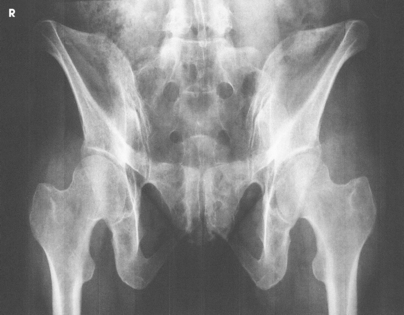

Structures shown: The image shows an AP projection of the pelvis and of the head, neck, trochanters, and proximal one third or one fourth of the shaft of the femora (Fig. 7-18).

Structures shown: The resulting image shows the head, neck, trochanters, and proximal one third of the body of the femur (Fig. 7-31). In the initial examination of a hip lesion, whether traumatic or pathologic in origin, the AP projection is often obtained using an IR large enough to include the entire pelvic girdle and upper femora. Progress studies may be restricted to the affected side.